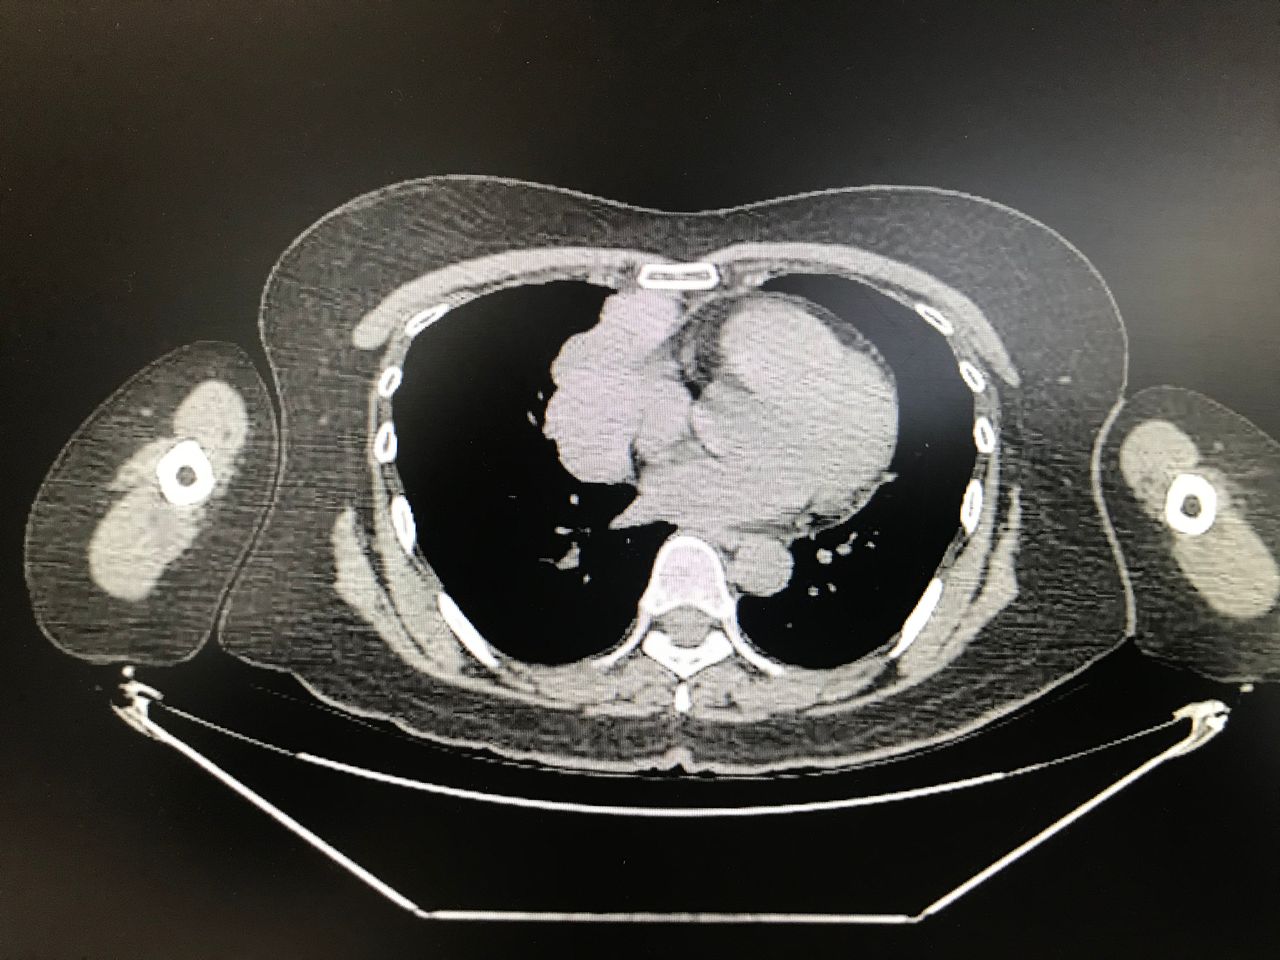

- ECOGRAFIA PLEURAL Y PULMONAR